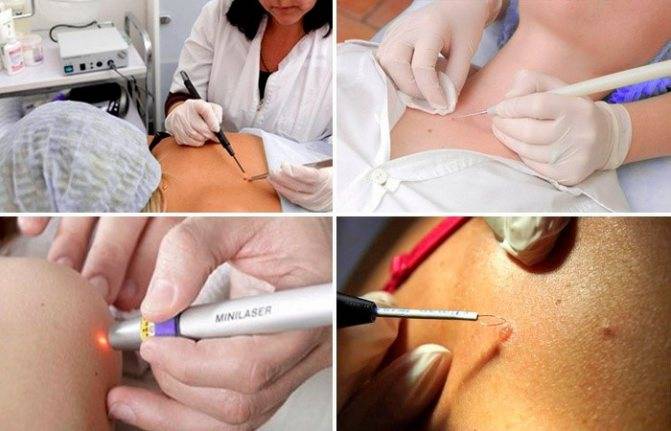

Они предлагают клиентам эффективные, быстрые и безболезненные аппаратные методы:

- криодеструкция (разрушение наростов жидким азотом);

- электрокоагуляция (прижигание электрическим током);

- лазерная коагуляция (испарение пораженных тканей эрбиевым излучением);

- радиоволновое удаление (луч тоже испаряет ткани, только электрод нагревают высокочастотные радиоволны).

Два последних метода – самые современные. Они позволяют удалять новообразование бесконтактно, не дотрагиваясь до кожи насадкой-электродом.

Энергия (световая, радиоволновая), направляемая кончиком коагулятора на нарост, заставляет воду в его клетках буквально закипать и испаряться.

В результате образование удается быстро и точно убрать, а окружающие ткани практически не страдают. Поле воздействия стерилизуется высокой температурой, поэтому вирус в клетках погибает, что позволяет снизить риск рецидива.

Нет крови и боли благодаря «запечатыванию» сосудов и нервных окончаний. После таких операций не остается следов и рубцов на коже.

Лазер и радионож избавляют даже от больших подошвенных бородавок, уходящих вглубь тканей более чем на 5 мм.

Однако лазерное и радиоволновое лечение требует сложного дорогого оборудования, подготовки специалистов для работы с ним, поэтому оба метода дорогостоящие.

- Радиоволновое удаление. Это хирургическая техника, в основе которой лежит разрушение клеток под воздействием волны. Процесс длится около 5-10 минут. После операции в большинстве случаев не наблюдается осложнений. Для удаления папиллом в чувствительных местах перед радиоволновым методом проводится анестезия.

- Криотерапия. Нарост прижигают жидким азотом. Пациент ощущает легкое жжение и холод. Через некоторое время после процедуры папиллома отпадает. Преимущество метода заключается в его безболезненности, а также в отсутствии рубцов после удаления.

- Электрокоагуляция. В основе лежит использование электрического высокочастотного тока. На поверхность папилломы и участка вокруг нее накладывается проводящий электрод. Далее пораженное место обрабатывают диатермическим ножом, в результате чего происходит мощное выделение теплоэнергии, и сосуды разрушаются. Процедура проходит быстро и безболезненно, а ранка заживает через несколько дней.

Лазерная терапия

Пожалуй, это самый популярный метод удаления новообразований на коже.

Фото: лазерное удаление

В его основе лежит воздействие лазерным лучом на тело папилломы. При помощи сверхкоротких последовательных волновых импульсов и происходит очищение кожи. Здоровый участок при этом не повреждается.